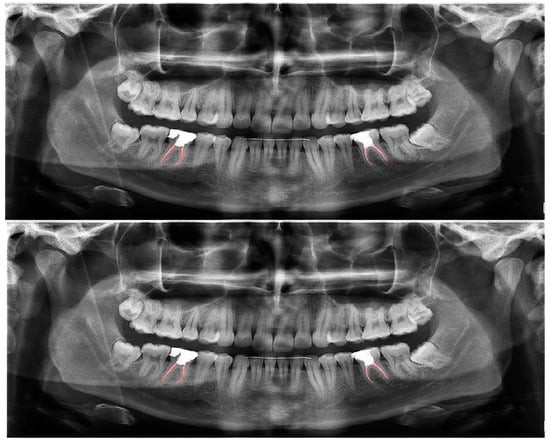

Figure 6.

Automatic segmentation of root-canal fillings. Manual segmentation (upper image) and automatic segmentation (lower image) can be seen above.

Figure 7.

Automatic segmentation of residual roots. Manual segmentation (upper image) and automatic segmentation (lower image) can be seen above.